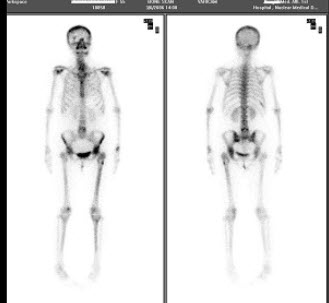

102、单项选择题

男,47岁,进行性消瘦贫血,全身疼痛1年。行全身骨显像如图,可能的诊断是()

A.大致正常的骨影像

B.代谢性骨病

C.多发性骨髓瘤

D.超级骨显像

E.广泛骨转移瘤